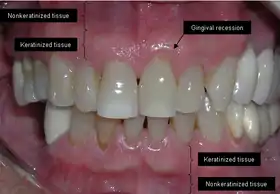

The soft tissue in the oral cavity is classified as either keratinized or nonkeratinized based on the presence of keratin in the epithelium.[4] In health, the soft tissue immediately around the teeth is keratinized and is referred to as keratinized tissue or gingiva. Alveolar mucosa is non keratinized oral epithelium and is located apical to the keratinized tissue, delineated by the mucogingival junction (MGJ). It should also be pointed out that mucosa can surround a tooth in health.[5] Nonkeratinized tissue also lines the cheeks (buccal mucosa), underside of the tongue and floor of the mouth. The lips contain both non-keratinized tissue (on the inside) and keratinized tissue on the outside, demarcated by the vermillion border. The dorsum of the tongue is keratinized and features many papillae, some of which contain taste buds.[6]

Exposure of the tooth root due to loss of keratinized tissue around the neck of a tooth is referred to as gingival recession. This can result in sensitivity or pain from the exposed tooth root surface (dentin is more permeable and soft compared to enamel and dentin is what makes up the tooth root).[7] Recession may also cause an unasthetic appearance especially if located in the anterior dentition (front teeth). While not all cases of gingival recession require surgical correction, there are various options if that is what the patient desires.[8] It should be reinforced that recession left untreated will not result in tooth loss, contrary to popular belief. Also, recession that is left untreated can be maintained and the inflammation kept at bay with proper brushing and oral hygiene technique.[5] On the other hand, if one desires to pursue corrective therapy, there are a wide variety of techniques ranging from autograft (your own tissue, usually taken from the palate), allograft (someone else's tissue, cadaver), xenograft (animal, usually porcine or bovine) or simply repositioning of the tissue native to the site.[9] The benefits of corrective therapy often result in decreased sensitivity through coverage of the root surface in addition to a gain in the keratinized tissue mentioned beforehand.